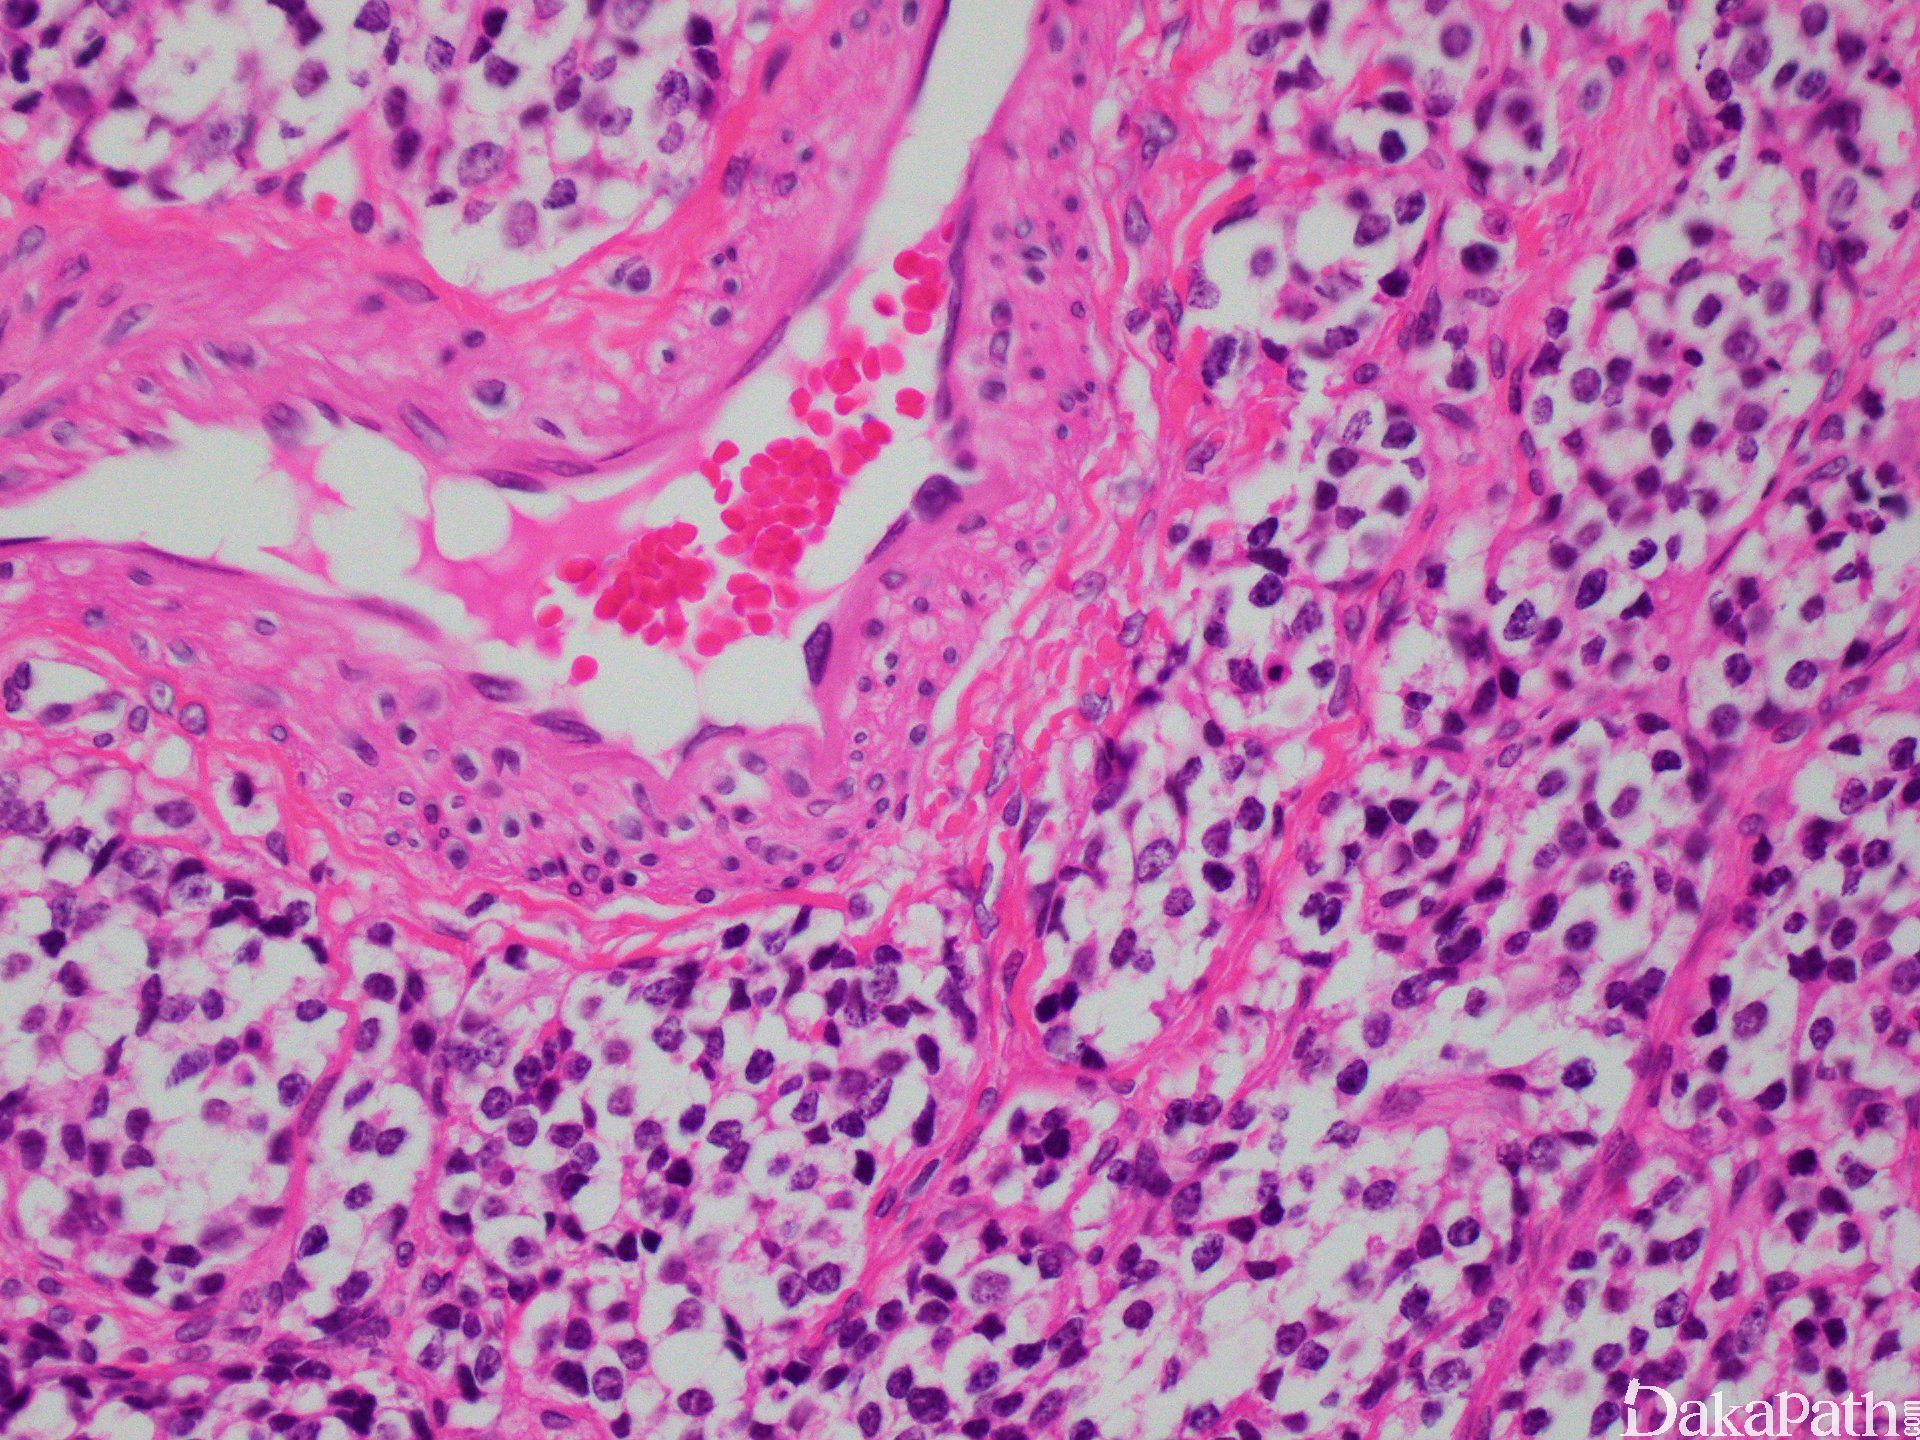

组织学改变基于分化成程度不同而呈不同,原始神经母细胞分叶状排列(不管分级如何)。叶状结构之间富于纤维血管间隔,支持细胞常位于细胞巢周边。

肿瘤细胞呈经典小圆蓝细胞,比成熟淋巴细胞稍微大一些,核浆比高,小而一致的胞核伴细致、椒盐样染色质分布,胞核比较小或缺席。细胞呈合胞体样。可见中央为神经丝状物构成的菊形团(Homer Wright)。

可见砂砾体样或凝结物样钙化,随着级别的增高,出现的频率降低。偶见血管浸润、神经节细胞或节细胞神经母细胞分化、含有黑色素细胞及横纹肌母细胞样细胞。